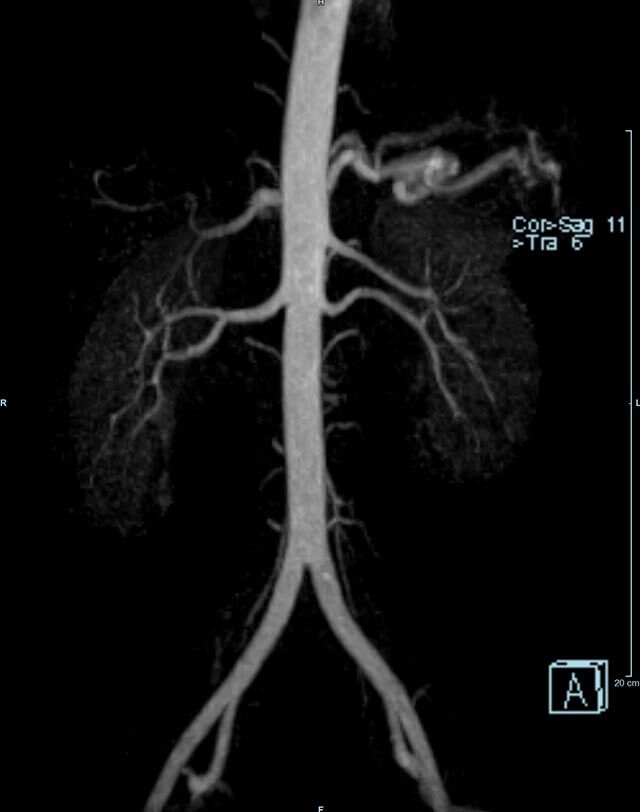

• Bauchgefäße

• Erfassung und Verlaufskontrolle bei arteriellen Aneurysmen (Aussackungen der Arterien), vor allem der Bauchaorta

• Darstellung von Gefäßengen an Nierenarterien, Baucharterien und Becken-/Beinarterien

• MR-Angiographie mit Kontrastmittel

• Erfassung arterieller und venöser Gefäße/Bypässe aller Körperregionen mit 3D-Rekonstruktion